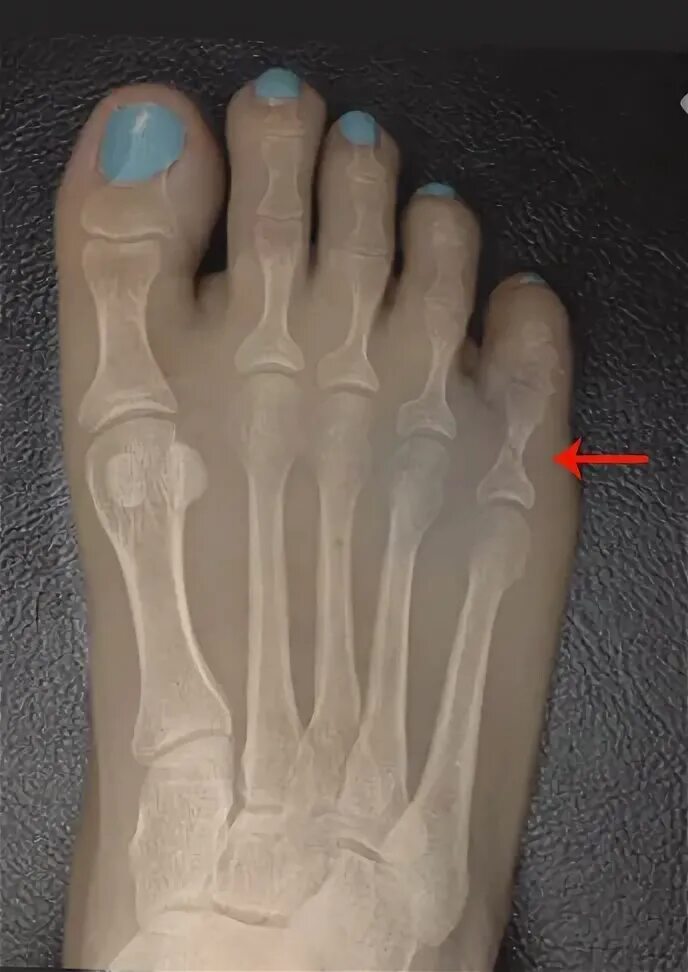

Закрытый перелом пальцев стопы мкб 10